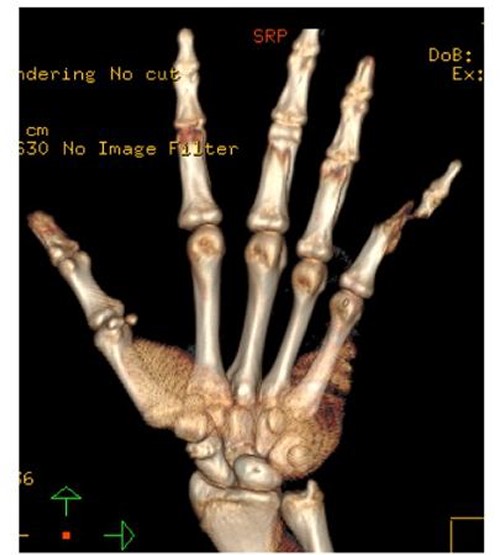

A 15-year-old boy, right handed, was not known to have any chronic medical illnesses. He presented to the emergency department (ED) with a history of severe left-wrist pain and swelling after falling from a height of 5–6 meters on an outstretched hand with the wrist in extension three hours prior to the ED presentation. The pain is mainly located in the left wrist’s dorsum and distal part of the forearm. Increasing pain with movement and relived with immobility. On examination, a normal-appearing wrist. No open wounds or lacerations, nor abrasions. There is no obvious deformity. There was mild swelling in the wrist. Tenderness over the dorsal radial wrist, including the anatomical snuff box. The range of motion was restricted due to pain. The neurovascular examination was normal. A plain radiograph in the ED showed a scaphoid tubercle fracture and a capital bone fracture. Initial radiographs are shown in Fig. 1). The patient was taken for computerized tomography (CT) to better define the extent of the injury (Fig. 2). A CT scan showed a displaced fracture of the capitate carpal bone, with an avulsion fracture at the distal tubercle of the scaphoid carpal bone, with extension to the articular surface. In addition to perilunate fracture, the rest of the carpal bone’s alignment is maintained. The patient was shifted to the operating room for open reduction and k-wire fixation of the scaphoid and capitate fracture of the left hand. Under general anesthesia, a tourniquet was applied. The incision was over the dorsal aspect of the left wrist, proceeding with the wrist capsule opening. The fracture was fixated with two Kirschner wires. Alignment was assured intraoperatively with an x-ray (Fig. 3). Plain radiographs post-fixation showed intact alignment. Postoperatively, the wrist was immobilized in a long-arm splint. The Kirschner wires and the protected splint were removed at 5 and 8 weeks, respectively. Immediately afterward, physiotherapy started. A few months following surgery, the site of the fracture healed radiologically. The patient had no pain, and the range of motion was acceptable after a period of physiotherapy. Figure 4 demonstrates a medical illustration of a scaphocapitate fracture.

Posteroanterior and oblique radiographs taken intraoperatively after fixation, demonstrating proper alignment of hardware.